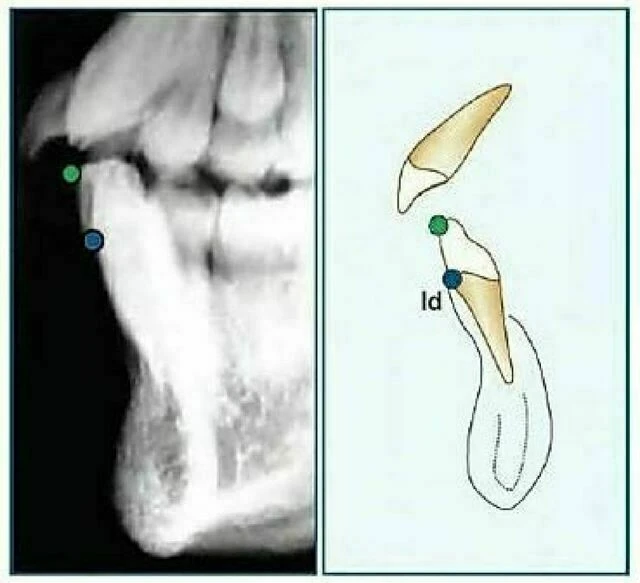

Insision Inferius (Ii): Đỉnh rìa cắn của răng cửa giữa hàm dưới nằm về phía ngoài nhất.

Infradentale (Id): Điểm nằm ở vị trí trên trước nhất của xương ổ răng hàm dưới, thường tìm thấy gần đường nối xi măng – men răng của răng cửa giữa hàm dưới. Còn được gọi là điểm Inferior Prosthion.